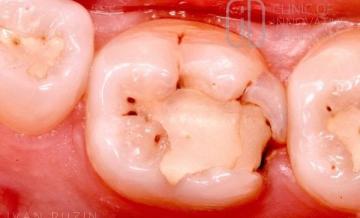

Художественная реставрация зуба 3.6 (пошаговый протокол)

76 Исходная ситуация. Поэтапный протокол: 1. Удаление старой реставрации и пораженных тканей зуба. Дистальный фрагмент зуба 3.6 препарировался без использования коффердама, с целью облегчения некркэтомии в данном фрагменте. После удаления всех нежизнеспособных тканей с дистального фрагмента был наложен коффердам на зубы 3.7 – 3.4 для лучшей визуализации рабочего поля. Удаление инфицированного дентина в глубоких слоях […]